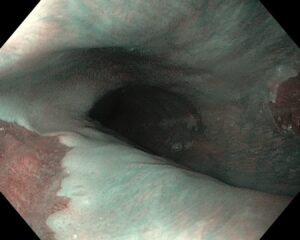

Атлас

В эндоскопическом атласе обычно представлены изображения и видео, полученные во время процедур, проводимых врачами-эндоскопистами. Эти изображения и видео могут использоваться для обучения студентов медицинских учебных заведений, повышения квалификации медицинских работников, а также для консультации врачей при диагностике и лечении различных заболеваний.